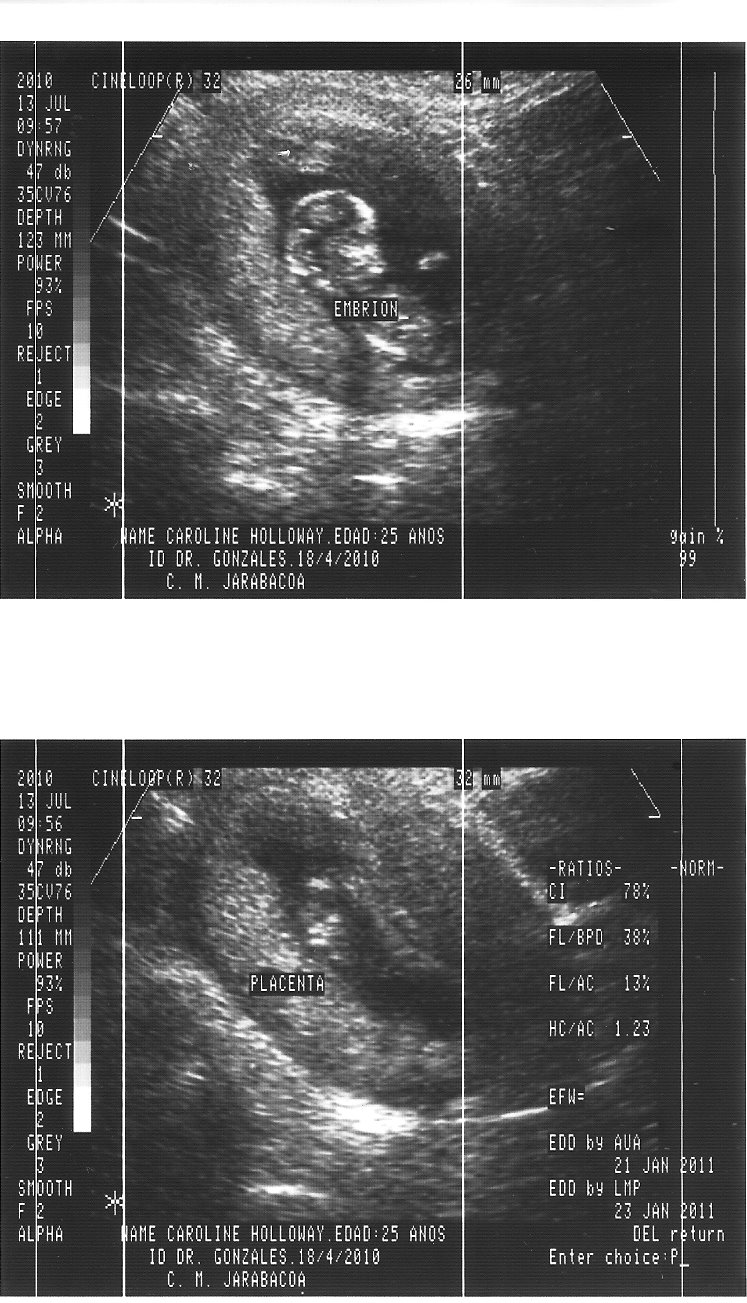

On Tuesday we had an ultrasound. It was the second one...but since I was only 4 weeks along on the first one...this is the first time (s)he actually looks like a baby instead of a dot. We were so excited to know that the baby continues to develop healthily, has a good heartbeat, and is already moving around! It's so crazy that (s)he already looks like a baby even though (s)he is only like 3 inches tall. Here are some ultrasound pictures. I don't know how good the quality is, but our families have been dying to see them :)

In these 2 pictures, the top one shows the whole baby and the bottom one is the placenta

Top- leg, middle- abdomen, bottom- head. All of which measured perfectly at 12 weeks!